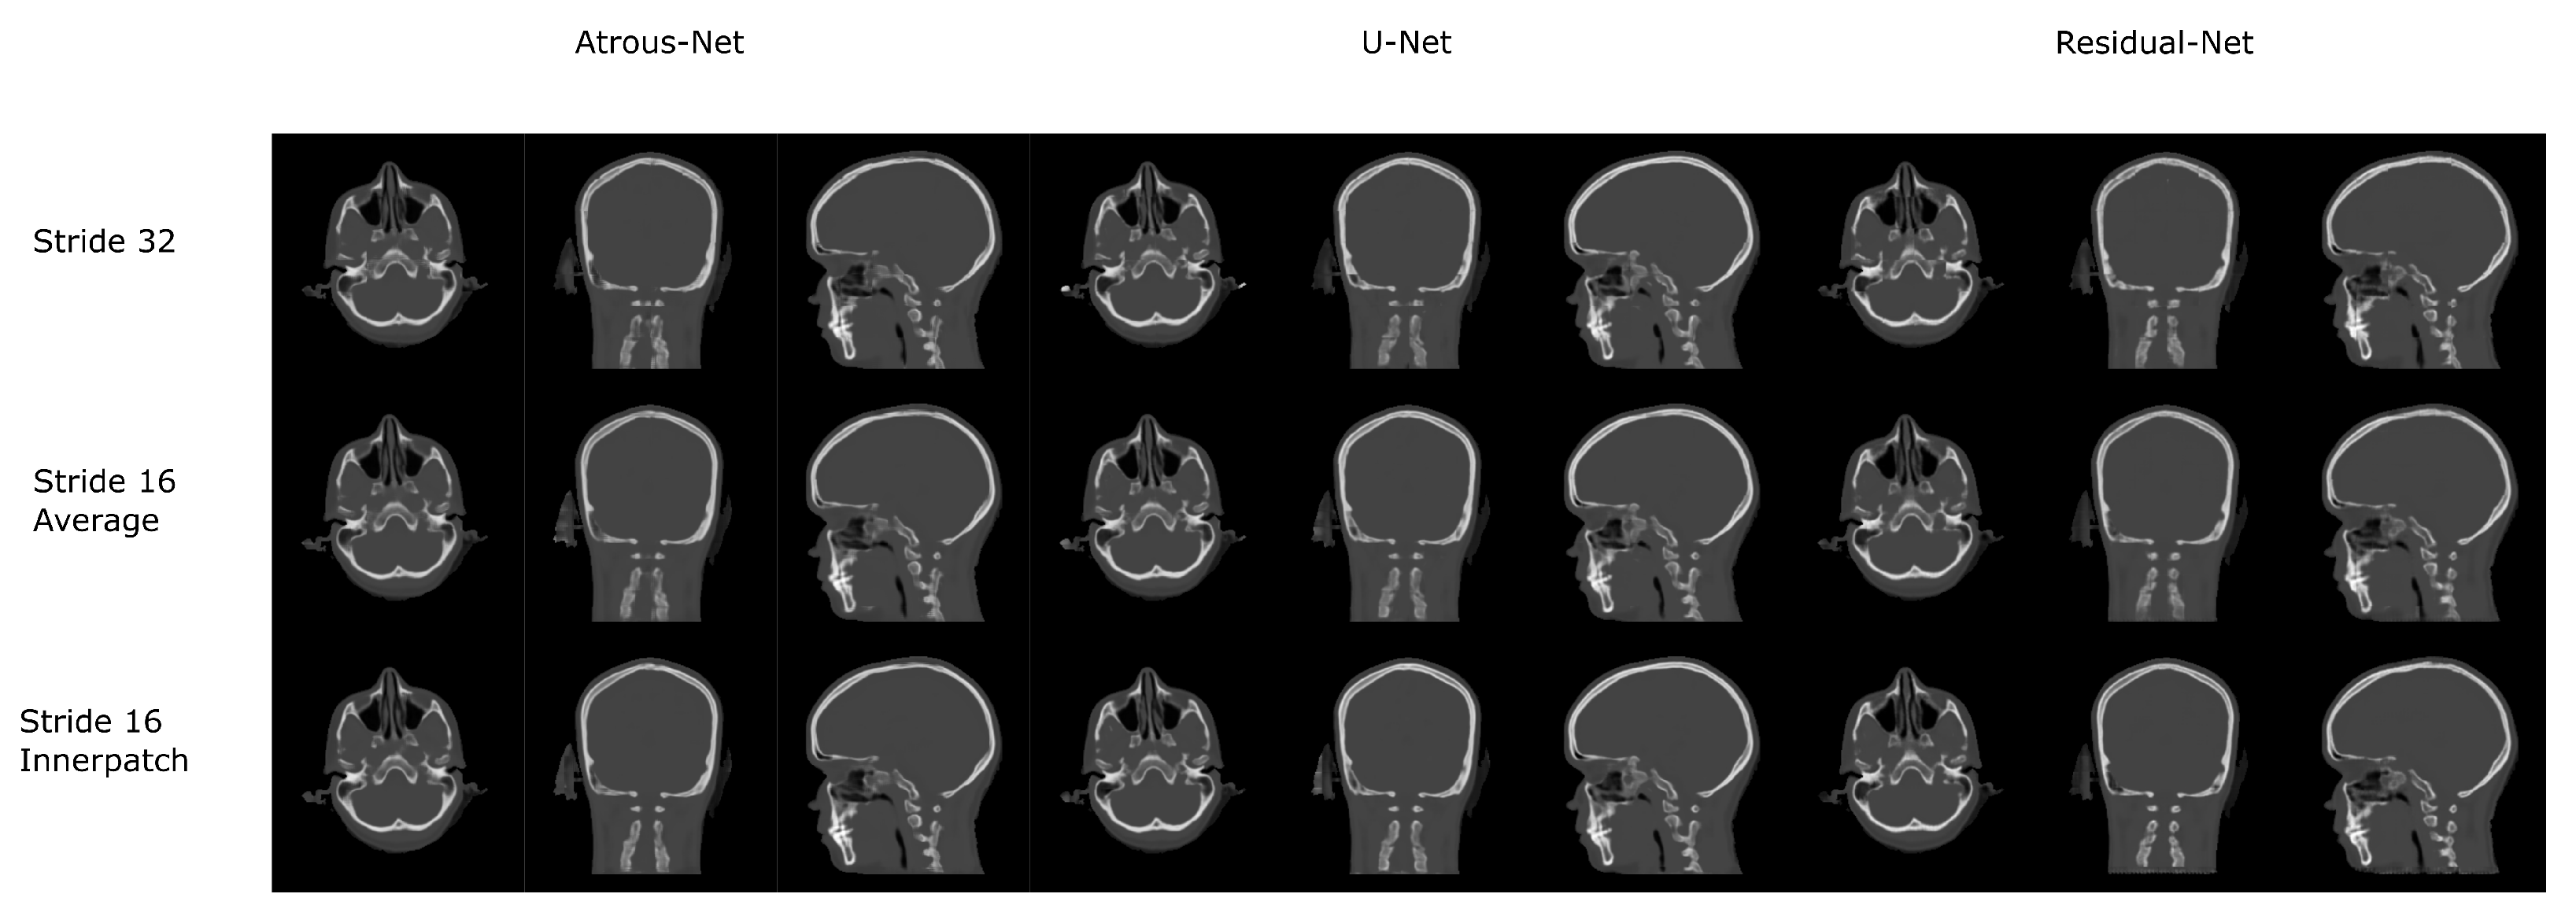

The results for all tissues using the head dataset are depicted in Table 1, Table 2 and Table 3; the results using only the bone voxels are detailed in Table 4, Table 5 and Table 6; the results using only the fat voxels are detailed in Table 7, Table 8 and Table 9; and the results using only the soft-tissue voxels are detailed in Table 10, Table 11 and Table 12. The best performing 2D network for the head dataset was the Residual-net. The results presented a MAE of 99.83 HU, a PSNR of 24.83 and a Pearson Coefficient of 0.931 in all tissues, and a MAE of 326.33 HU, a PSNR of 19.04 and a Pearson Coefficient of 0.826 in bone voxels. The ANOVA test revealed a statistically significant effect of the 2D architectures for MAE results (all tissues: , ; bone: , ) and PSNR results (all tissues: = 99.3, ; bone: = 85.6, ). A paired t-test was used to compare the Residual-net to the other networks reporting also statistically significant differences in the MAE and in the PSNR (Table 13). Using 2D convolutions, the Atrous-net and the U-net performed 5% and 18% worse than the residual-net, respectively. Moreover, the U-net network was clearly behind the other networks using 2D convolutions. Nevertheless, the U-net in 3D-16 obtained a MAE of 89.54 HU, a PSNR of 25.69 and a Pearson Coefficient of 0.943 in all tissues, and a MAE of 289.10 HU, a PSNR of 20.05 and a Pearson Coefficient of 0.861 in bone voxels, which were the best results for the head dataset. The ANOVA test also reported a statistically significant effect of the 3D networks for the MAE (all tissues: ; bone , ) and the PSNR (all tissues: , ; bone: , ). The post hoc paired t-test that is depicted in Table 14 also reported statistically significant differences in the MAE and PSNR after comparing each architecture. Summarizing, the results using 3D convolutions from the U-net were 17% and 10% better than those of the Atrous-net and Residual-net, respectively. Visual result examples of head pseudo-CTs are depicted in Figure 6 and Figure 7. Table 15 shows the time needed to synthesize a whole head volume using the different architectures.

Figure 6.

Head results using 2D networks.

Figure 7.

Head results using 3D-16 networks.

3.4. 3D Reconstruction Results

Figure 10 and Figure 11 show the results of the three merging strategies that have been tested: stride 32, stride 16 with averaging of overlapping voxels and stride 16 considering the inner cube. The average time to synthesize a volume is shown in Table 15 and Table 30. The first method—referred as “stride 32” in Figure 10 and Figure 11—generated artifacts in the boundaries of the cube and misalignment in the bone and air structures. Moreover, this approach showed a greater error than the other two in the quantitative results. Nevertheless, this method was quite fast, generating a volume in 8–19 s. The other two methods provided, in average, a similar quantitative result, being the use of the inner cube slightly better. However, the use of stride 16 increased the time to generate a pseudo-CT volume up to 58–90 s. According to the averaging strategy, some artifacts can be noticed in the boundaries of the cubes after a visual inspection of the results.

Figure 10.

Comparison between the reconstruction method proposed.

According to the results of the current work, there is no preferred network for every problem. Thus, the results depend on the specific anatomy defining the problem and the MRI sequence that is used. As shown in Section 4. Results, if the anatomy is similar to a head with complex bone structures and geometries, 2D schemes generate aliasing and artifacts across bone structures. Instead, 3D schemes and reconstructions with stride 16 provide bones with smooth boundaries, which is translated into a significant reduction of the error. Moreover, the best architecture to achieve the best detail in a head pseudo-CT is the 3D U-net (). When using 3D architectures, the input of the network is usually a 3D patch due to GPU memory limitations. 3D patches only depict a part of the anatomy. Therefore, they provide limited contextual information. In this case, the progressive spatial reduction and up-sampling of the feature maps are probably the best option, as it occurs in the U-net.